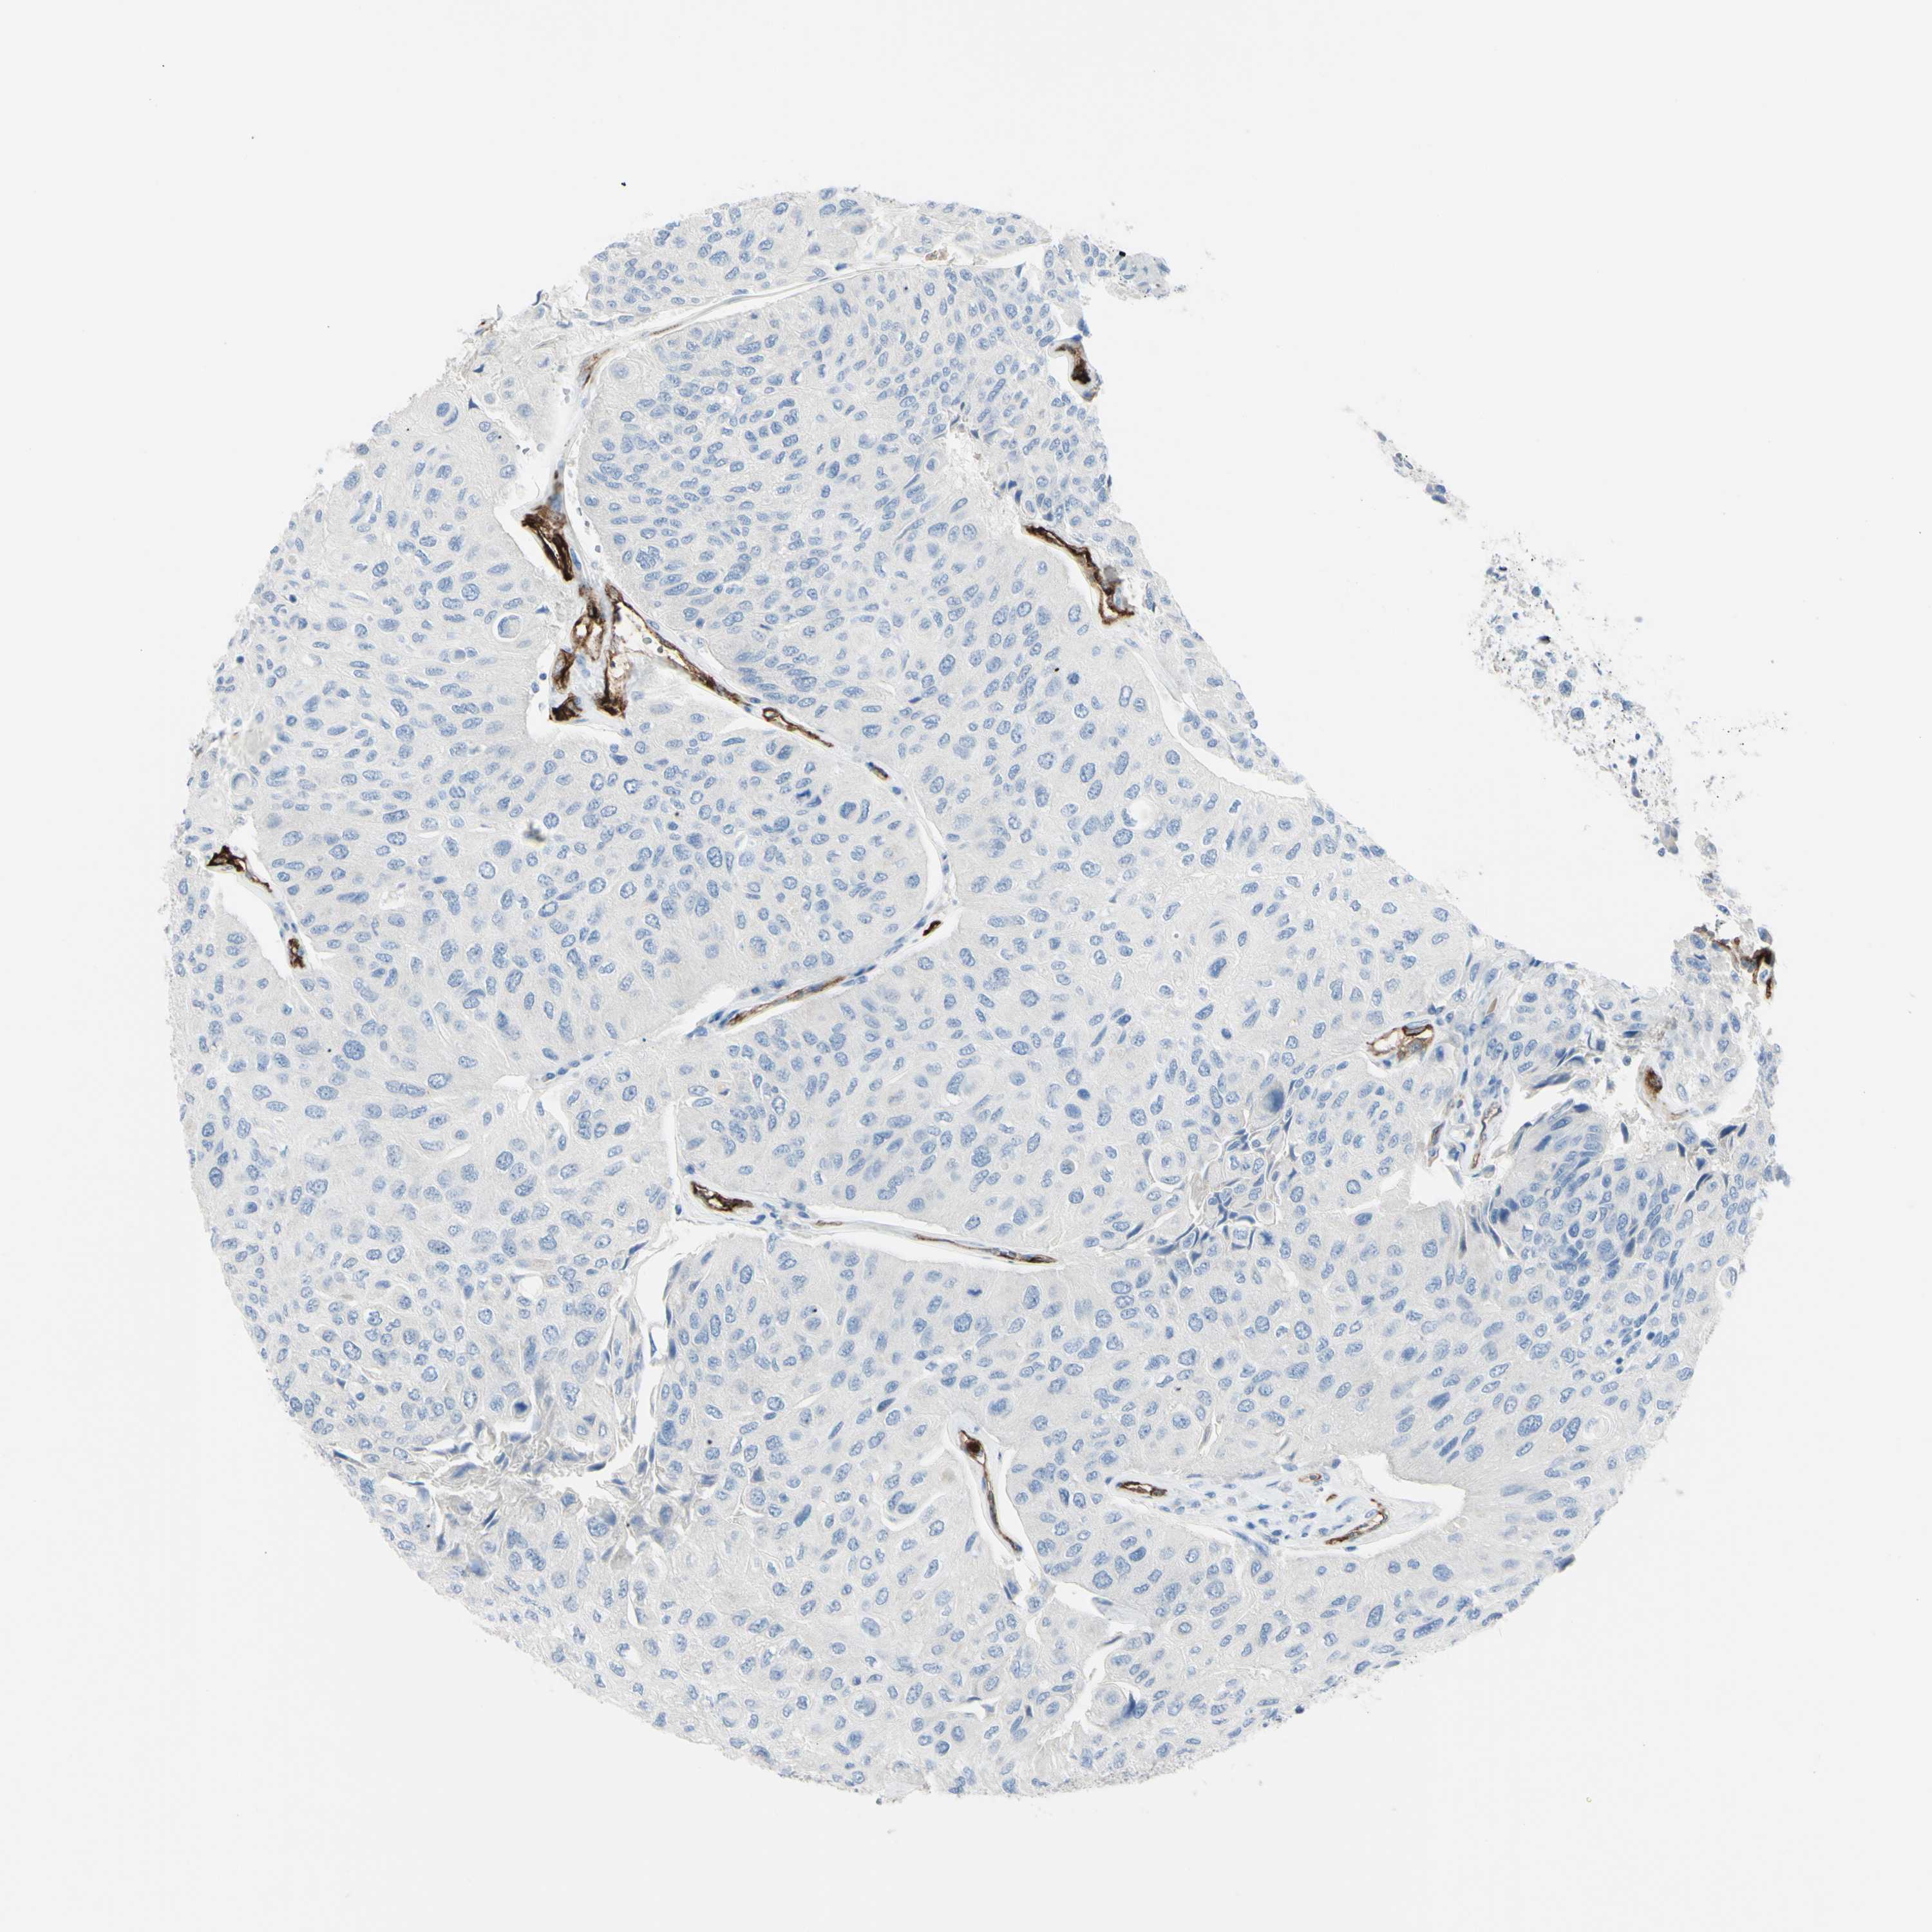

UROTHELIAL CANCER - Protein expressioni

A mouse-over function shows sample information and annotation data. Click on an image to view it in a full screen mode. Samples can be filtered based on level of antibody staining by selecting one or several of the following categories: high, medium, low and not detected. The assay and annotation is described here.

Note that samples used for immunohistochemistry by the Human Protein Atlas do not correspond to samples in the TCGA dataset.

Antibody stainingi

Antibody staining in the annotated cell types in the current human tissue is reported as not detected, low, medium, or high, based on conventional immunohistochemistry profiling in selected tissues. This score is based on the combination of the staining intensity and fraction of stained cells.

Each image is clickable and will lead to virtual microscopy that enables deeper exploration of all samples and also displays staining intensity scores, fraction scores and subcellular localization as well as patient and tissue information for each sample.

Antibody HPA010593

Antibody CAB001451

Staining

High

Medium

Low

Not detected

Intensity

Strong

Moderate

Weak

Negative

Quantity

>75%

75%-25%

<25%

None

Location

Nuclear

Cytoplasmic/membranous

Cytoplasmic/membranous,nuclear

Urothelial carcinoma, Low grade

Urothelial carcinoma, High grade

Adenocarcinoma, NOS